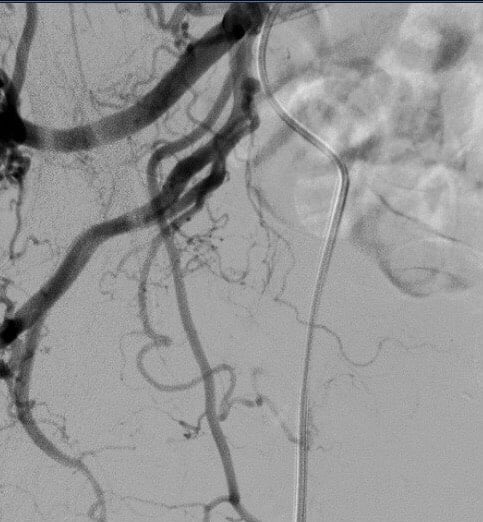

Với vị thế là một đơn vị hàng đầu Việt Nam, Trung tâm Điện quang Can thiệp Bạch Mai đã thực hiện hơn 1.000 ca phì đại tuyến tiền liệt bằng phương pháp nút động mạch – những trường hợp từ tuyến dưới không thực hiện được, cũng như các trường hợp khó nhất, bệnh nhân cao tuổi nhất hay những trường hợp phẫu thuật, nội khoa thất bại đều được can thiệp thành công. Tuy nhiên, với trường hợp bệnh nhân Nguyễn Văn T là một thách thức vô cùng lớn đối với các can thiệp viên. Bệnh nhân nhiều tuổi, tiền sử cao huyết áp nhiều năm nên mạch máu giãn ngoằn ngoèo, kết hợp với bệnh tiểu đường nên rất nhiều xơ vữa vôi hóa gây hẹp tắc mạch máu. Bằng con mắt của can thiệp viên có nhiều kinh nghiệm, bác sĩ Phan Hoàng Giang chia sẻ: Gốc xuất phát của động mạch tuyến tiền liệt, động mạch bàng quang trên, động mạch bàng quang dưới và động mạch chậu tạo thành ngã tư rất khó chọn lọc vào nhánh nuôi tuyến tiền liệt. Ngoài ra ngay vị trí xuất phát, động mạch tuyến tiền liệt xoắn đúng 1,5 vòng nhỏ (do bệnh nhân cao huyết áp). Để có thể tiến hành ca can thiệp cho người bệnh, ngoài kiến thức chuyên môn sâu, kỹ năng lành nghề, các can thiệp viên phải vận dụng toàn bộ trí lực để tối ưu nhất hiệu quả của ca can thiệp.

Mô tả lại tiến trình can thiệp, BS Giang vẫn còn cảm thấy hạnh phúc bởi kíp kỹ thuật đã tạo nên một kỳ tích trong lịch sử y học Việt Nam và cũng chưa từng có trong y văn thế giới. “Khi thực hiện nút mạch cho bệnh nhân, sau khi hoàn thành 1 bên hoàn toàn tốt, chúng tôi thực hiện bên còn lại thì gặp khó khăn do 3 gốc động mạch tuyến tiền liệt, động mạch bàng quang dưới, động mạch bàng quang trên được tách ra cùng vị trí của động mạch chậu trong tạo thành ngã tư rất khó chọn lọc vào động mạch tuyến tiền liệt. Sau những phút nỗ lực cực điểm để tiếp cận được nhánh này thì chúng tôi lại còn ngỡ ngàng hơn, khi động mạch tuyến tiền liệt rất bé, ngắn, lại còn xoắn đúng 1,5 vòng. Với sự thành thạo kỹ thuật của kíp can thiệp, cùng với việc sử dụng khéo léo các vi ống thông và vi dây dẫn siêu nhỏ cỡ dưới 0.010”, kíp can thiệp đã thành công để có thể đi qua được “vòng xoắn” đó và tiếp cận siêu chọn lọc động mạch tuyến tiền liệt.

| Chụp động mạch chậu trong cho thấy động mạch tuyến tiền liệt tách ra từ vị trí khó | Hình ảnh cho thấy động mạch tuyến tiền liệt tách ngay gần động mạch bàng quang trên, dưới đồng thời xoắn 1,5 vòng | Động mạch tuyến tiền liệt sau khi qua được vị trí khó khăn | Chụp mạch kiểm tra lại sau gây tắc hoàn toàn bằng hạt và tắc gốc bằng keo histoacryl |